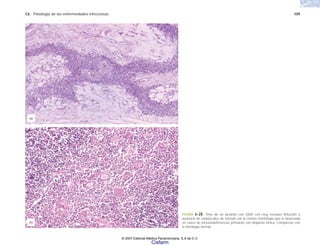

FIGURA 6-1. Ultraestructura de los macrófagos en la rata. a) Macrófago peritoneal. b) Macrófago alveolar.

(a)